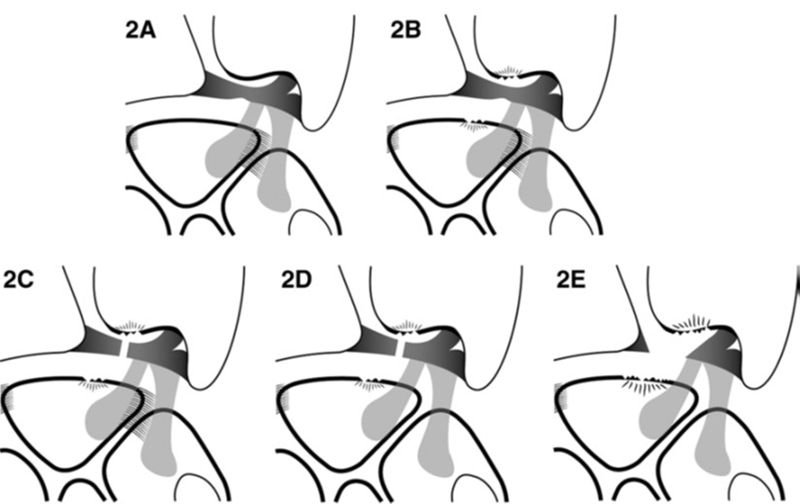

TFCC损伤机制

典型受伤机制为前臂旋前、腕关节过伸位时腕尺侧受到直接撞击或牵拉。多在以下场景受伤:网球、高尔夫球、羽毛球等运动者手腕尺侧受力和快速扭转活动;车祸中司机手握方向盘腕部受到旋转牵张暴力;突然摔倒时用手撑地;提重物不慎或手腕用力不当时扭伤等。